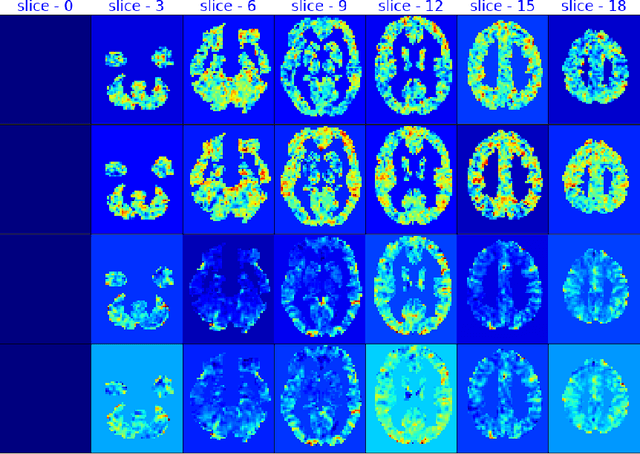

Abstract:fMRI semantic category understanding using linguistic encoding models attempts to learn a forward mapping that relates stimuli to the corresponding brain activation. Classical encoding models use linear multivariate methods to predict brain activation (all the voxels) given the stimulus. However, these methods mainly assume multiple regions as one vast uniform region or several independent regions, ignoring connections among them. In this paper, we present a mixture of experts model for predicting brain activity patterns. Given a new stimulus, the model predicts the entire brain activation as a weighted linear combination of activation of multiple experts. We argue that each expert captures activity patterns related to a particular region of interest (ROI) in the human brain. Thus, the utility of the proposed model is twofold. It not only accurately predicts the brain activation for a given stimulus, but it also reveals the level of activation of individual brain regions. Results of our experiments highlight the importance of the proposed model for predicting brain activation. This study also helps in understanding which of the brain regions get activated together, given a certain kind of stimulus. Importantly, we suggest that the mixture of regression experts (MoRE) framework successfully combines the two principles of organization of function in the brain, namely that of specialization and integration.

Abstract:fMRI semantic category understanding using linguistic encoding models attempt to learn a forward mapping that relates stimuli to the corresponding brain activation. Classical encoding models use linear multi-variate methods to predict the brain activation (all voxels) given the stimulus. However, these methods essentially assume multiple regions as one large uniform region or several independent regions, ignoring connections among them. In this paper, we present a mixture of experts-based model where a group of experts captures brain activity patterns related to particular regions of interest (ROI) and also show the discrimination across different experts. The model is trained word stimuli encoded as 25-dimensional feature vectors as input and the corresponding brain responses as output. Given a new word (25-dimensional feature vector), it predicts the entire brain activation as the linear combination of multiple experts brain activations. We argue that each expert learns a certain region of brain activations corresponding to its category of words, which solves the problem of identifying the regions with a simple encoding model. We showcase that proposed mixture of experts-based model indeed learns region-based experts to predict the brain activations with high spatial accuracy.